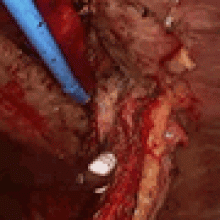

![]() |

| Figure 1. Camera port and working incision. |

The camera port is placed slightly posterior to the anterior superior iliac spine line in the 7th or 8th intercostal space. The working incision is placed in line with the major fissure usually in the 5th intercostal space in the mid axillary line (Figure 1). The muscles of the chest wall are divided carefully with cautery until the intercostal space is reached. Retraction using army-navy retractors in the superior and inferior aspect of the wound help with exposure. The intercostal space is identified when the rib cage is reached and using a finger, blunt dissection is performed posteriorly and anteriorly to separate the other muscles of the chest wall from the intercostal space. Low cautery settings are used to decrease the risk of thermal injury to the neurovascular pedicle. An incision is made in the intercostal muscle where it attaches to the lower rib for the length of the working incision. The intercostal muscle is then detached from the superior aspect of the lower rib after entering the pleural cavity using a combination of cautery and blunt dissection. This can be done gently with a periosteal elevator or a peanut dissector. An army-navy or Richardson retractor can be used to retract the anterior aspect of the incision to allow for mobilization greater than the length of the working incision. This is also done posteriorly. The superior aspect of the flap is left attached to the under surface of the upper rib in the intercostal space at this time to avoid potential damage to the vascular pedicle of the flap from passage of instruments through the working incision during the operation. However, when the intercostal space is narrow, mobilization of both superior and inferior aspects of the flap can be performed initially to allow more room for passage of instruments through the space and less trauma to the flap. Dissection of the superior aspect of the flap is done by incising the intercostal muscle where it attaches to the inferior edge of the upper rib in the intercostal space. The muscle is detached from the under surface of the rib using a combination of blunt and cautery dissection. The blade of the cautery is used for blunt dissection while inferior traction is placed on the muscle using a Debakey forceps or peanut dissector. The pleural cavity is entered early as this enables traction on the flap using a finger and allowing for the parietal pleura of the flap to be divided first allowing an easier and safer dissection of the vascular pedicle. Complete mobilization of the ICM is not performed initially because it can obstruct the view and hinder dissection during the pulmonary resection. There is no retraction of the intercostal space that would injure the flap during VATS lobectomy, therefore, there is little benefit in harvesting the entire flap prior to the lung resection.